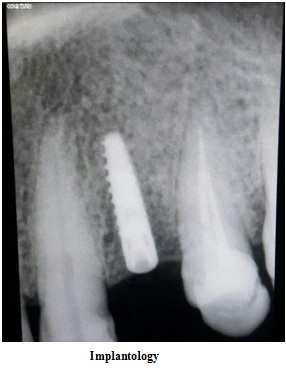

INVESTIGATIONS

Radiovisiography

Intra Oral Radiography Machine - Conventional and Digital

Laboratories / Facilities